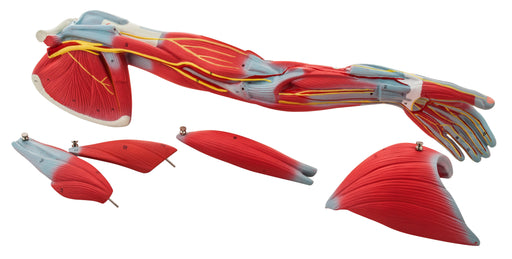

Muscular Arm - 6 Parts

This muscled arm model illustrates both the superficial and deeper muscles, five of which are removable from the muscled arm. Tendons, vessels, ner...

View full detailsam16030 -

Muscular Arm Large - 6 Parts

6 Part Model showing the muscles, tendons, blood vessels and nerves of the arm, hand and shoulder. Five muscles can be removed to reveal structure ...

View full detailsAM16076 -